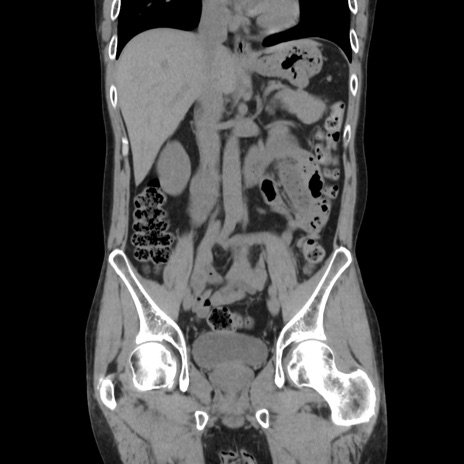

症例37(冠状断像)

【症例】40歳代 男性

【主訴】腹痛

【現病歴】4時間ほど前に電車に乗車中に臍部上より腹痛出現。徐々に増悪し起立困難となり、救急外来受診。生ものは数日食べていない。今朝お雑煮を食べた。

【身体所見】BT 36.8℃、BP 117/84mmHg、HR 91/min、SpO2 97%、苦悶様、腹部:臍上部広範囲圧痛あり、反跳痛±

【データ】WBC 8100、CRP 0.03